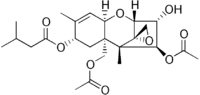

| IUPAC name

(2α,3α,4β,8α)-4,15-bis(acetyloxy)-3-hydroxy-12,13-epoxytrichothec-9-en-8-yl 3-methylbutanoate | |

| C24H34O9 | |

This compound has a tetracyclic sesquiterpenoid 12,13-epoxytrichothene ring system, which relates it to the trichothecenes.[10] These compounds are generally very stable and are not degraded during storage/milling and cooking/processing of food. They do not degrade at high temperatures either. This compound has an epoxide ring, and several acetyl and hydroxyl groups on its side chains. These features are mainly responsible for the biological activity of the compound and make it highly toxic. T-2 mycotoxin is able to inhibit DNA and RNA synthesis in vivo and in vitro[11] and can induce apoptosis.[12] However, in vivo the compound rapidly metabolizes to HT-2 mycotoxin (a major metabolite).[13]